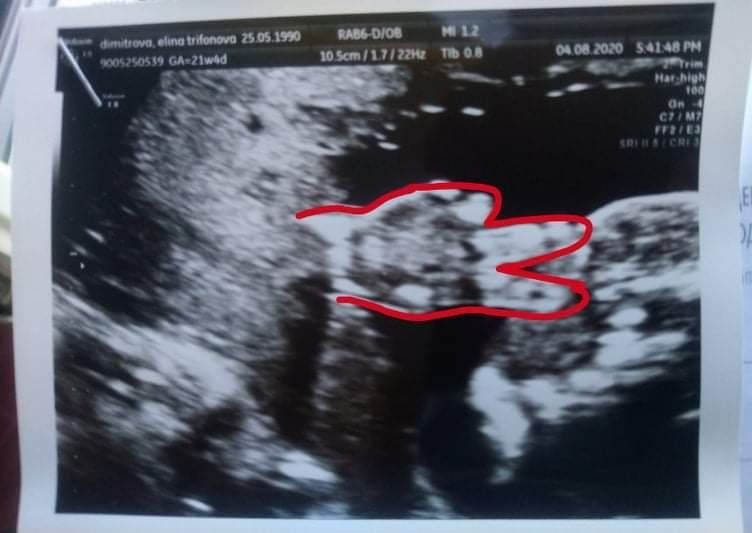

Мисля да се пробвам някъде за второ мнение , но ме съмнява да намеря някъде и то в отпускарския месец. Сега съм по-спокойно, видях и че нухалната гънка е 4,7мм което е добре за 21гс+4. Утре на трезва глава ще го мисля. Иначе бебо е много голям 550гр. Не спря да шава и не искаше да си покаже лявата ръчичка, накрая я изкара и направи знака за "мир"😂 Все едно ми каза "Спокойно, мамо, всичко с мен в наред"💙😭 Прилагам и снимка. Много се радвам, че мога да споделям в вас, момичета 💙